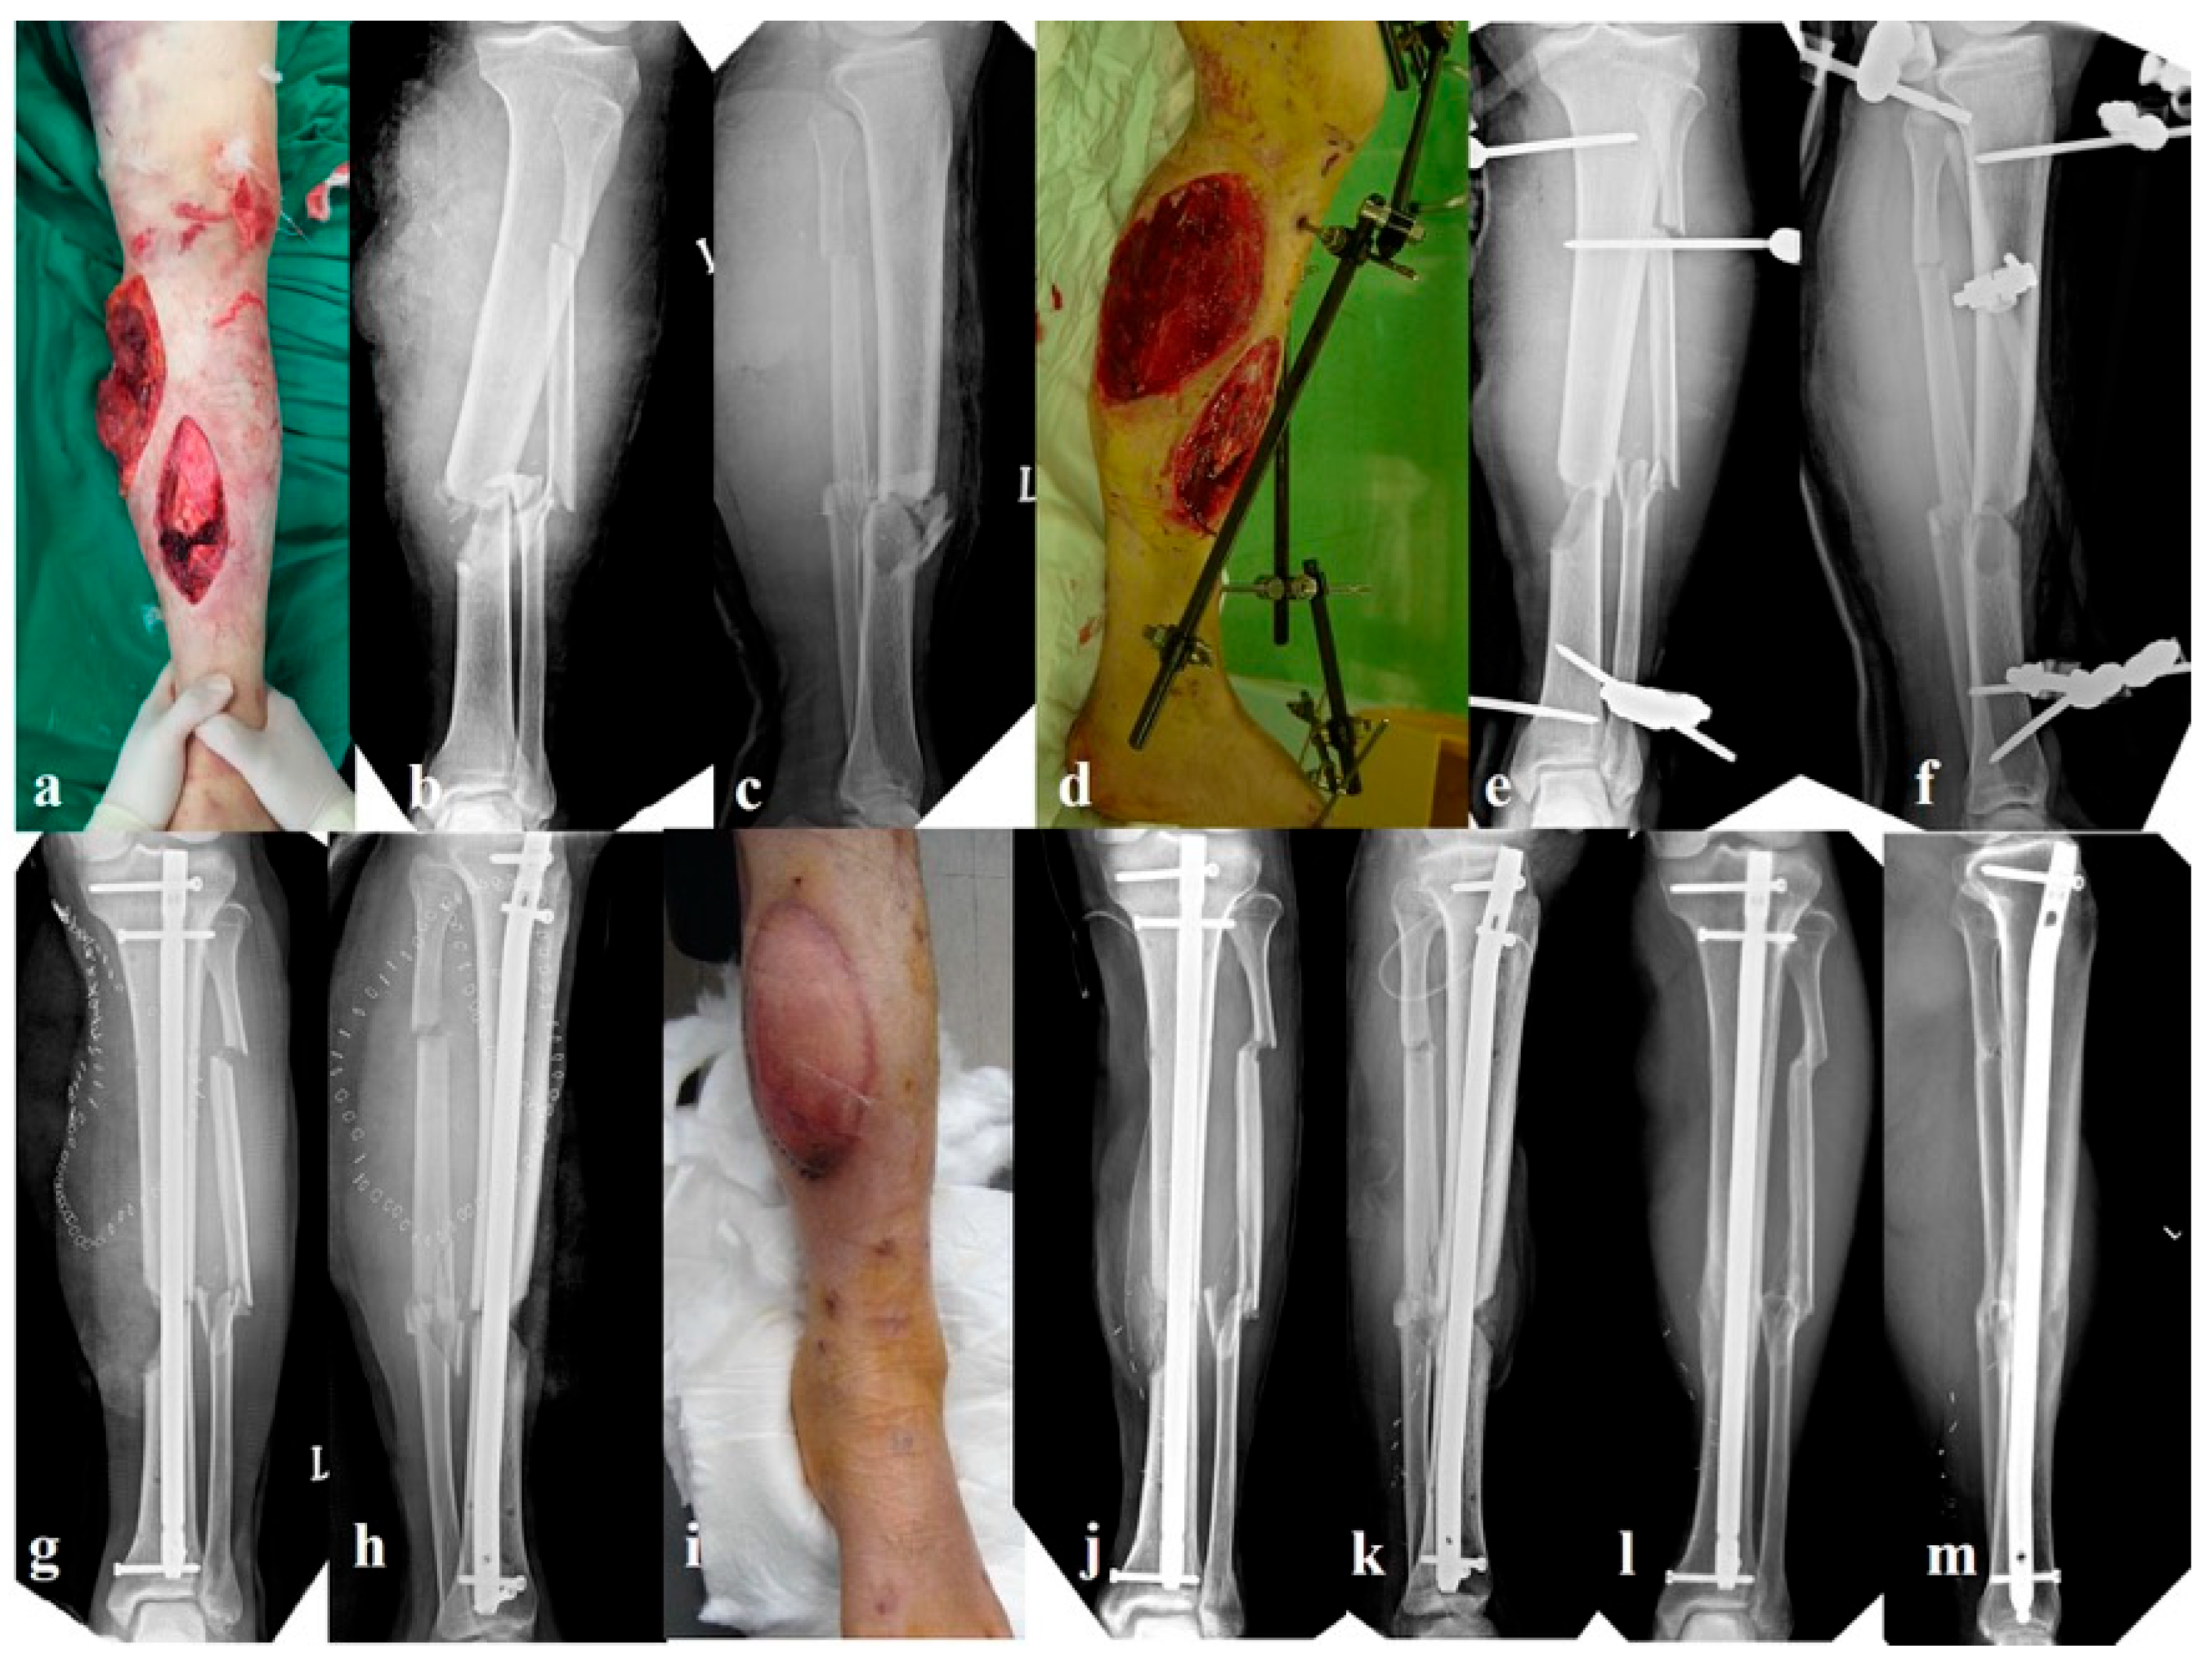

2.2.2. Group B: External Fixation Alone (n = 27, Figure 2)